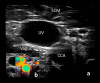

Neuromuscular ultrasound (NMUS) is becoming a standard element in the evaluation of peripheral nerve and muscle disease. When obtained simultaneously to electrodiagnostic studies, it provides dynamic, structural information that can refine a diagnosis or identify a structural etiology. NMUS can improve patient care for those with mononeuropathies, polyneuropathy, motor neuron disease and muscle disorders. In this article, we present a practical guide to the basics of NMUS and its clinical application. Basic ultrasound physics, scanning techniques and clinical applications are reviewed, along with current challenges.